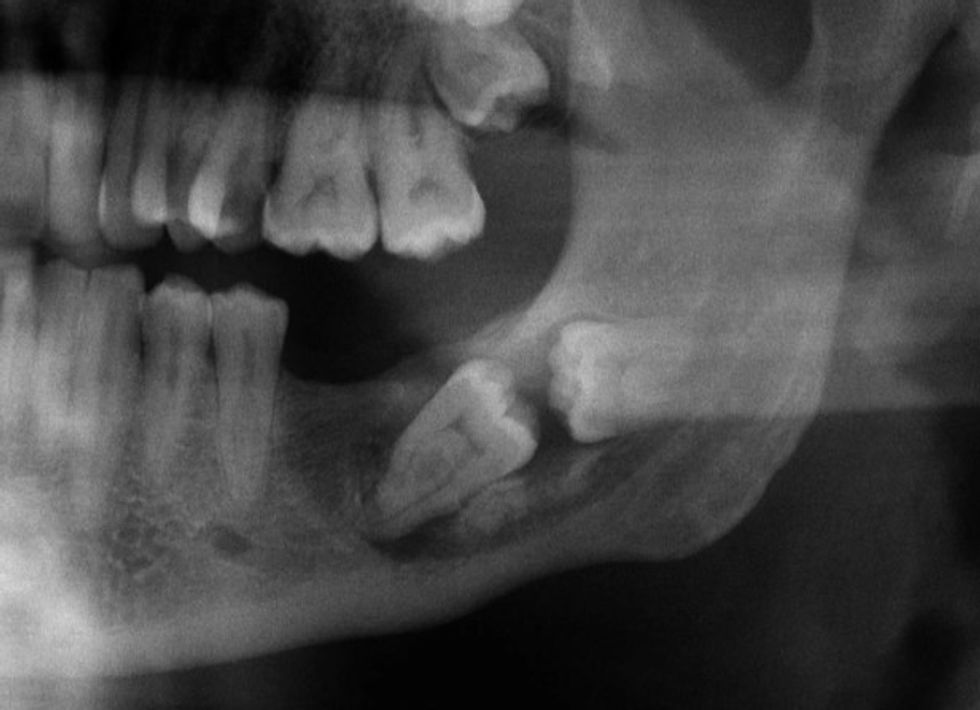

Tipare të pazakonta të trupit të njeriut që i bëjnë "pronarët e tyre" unik

Këtu janë disa njerëz, të cilët ishin më se të lumtur për të ndarë fotot e asaj që i bën ata kaq të veçantë. /Telegrafi/